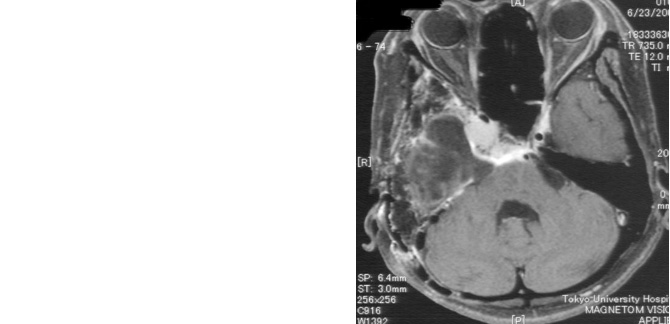

症例2

症例2は巨大斜台髄膜腫の症例です。歩行障害・嚥下困難などの症状をもち来院されましたが、腫瘍の大半を切除し、歩いて帰宅することが出来ました。海綿静脈洞部分の腫瘍は取ると合併症が出現するため、この部分は意図的に残しガンマナイフ治療を計画しています。

図2 頭蓋底髄膜腫 48歳女性 歩行障害、嚥下困難で来院

術後MRI:海綿静脈洞への浸潤部を除き

摘出、歩行障害改善し退院